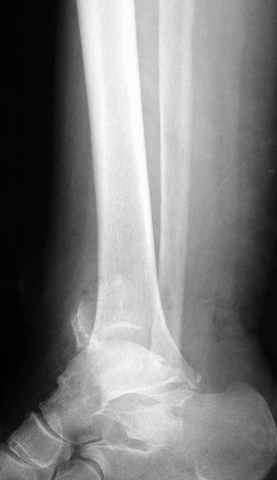

Pilon fracture:

ET> ЕЧ При подобных переломах фиксация малоберцовой кости обеспечивает

ET> низведение латерального тибиального фрагмента - появляется ориентир для

-Появляется ориентир и остов, на чем можно строить восстановление, почему сперва малоберцовую, впервые обьяснили и описали (Pylon type and Ankle fractures) в середине 50х Rienau и Gay.

Восстановливая длину и ротацию малоберцовой кости, затем относительно легче произвести реставрацию остальных элементов перелома дистального эпиметафиза болшеберцовой кости.

первую очередь, затем остальных элементов - стал классическим при лечении данной патолгии. Латеральная колонна (столб), дистальный

конец малоберцевой кости, к нему прикрепляется латеральный суставной фрагмент дистального эпиметафиза большеберцовой кости (как на снимке)

и таранная кость, которые при репозиции малоберцовой кости репонируются автоматически.

При косых переломах малоберцовой кости применение пластин отличается от обычных, показание antiglade technique-методика против скольжения, потому что укорочение длины малоберцовой кости чреваты ранними артрозами.

Из работ Ramsey and Hamilton, Yablon et., укорочения на 1мм

малоберцовой кости, уменьшает на 42% контактную поверхность между

малоберцевой и таранной кости, которое в свою очередь приводит к

увеличению давления на остальные части суставной поверхности, что

является предпосылкой раннего артроза.